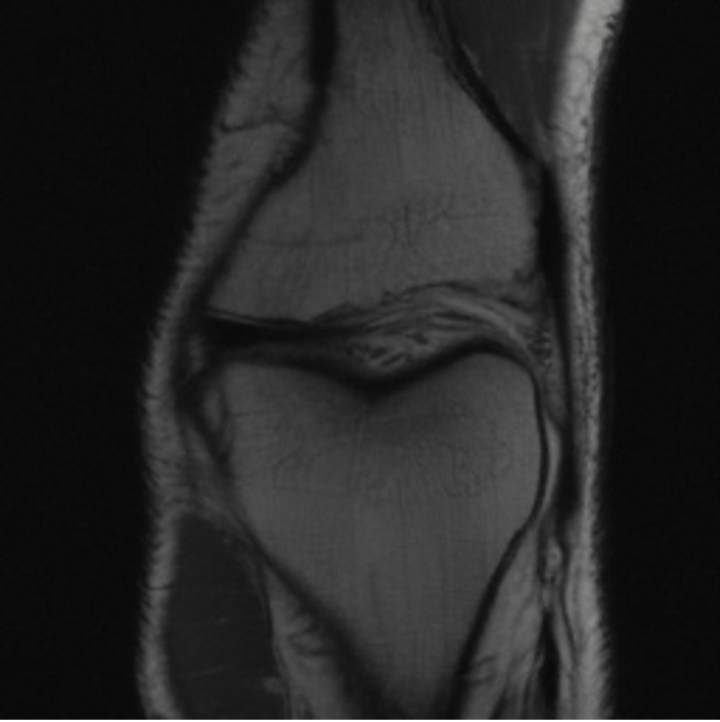

5.3 Out-of-Domain Generalisation

One way to test the generalization capability of the trained X-Diffusion is to test it on a completely different domain from an MRI dataset not seen during training. We report the single-slice results on NYU fastMRI [37, 82], a knee MRI dataset, using the X-Diffusion trained on the BRATS brain MRIs. The results are shown in Figure 9 and Table 2. It shows how successfully X-Diffusion is able to generate knee MRIs from a single image, despite not seeing knees at all in training. To qualitatively assess how realistic our generated 3D volumes were (produced from a single slice), we gave 20 generated examples alongside their real MRI counterparts to an expert orthopaedic surgeon. He was then asked to identify the real example from a given pair. The surgeon identified with certainty only 10 real knee MRIs out of 17, while could not decide on the remaining 3 of the 20 MRI pairs. This further validates the generated out-of-domain MRIs.